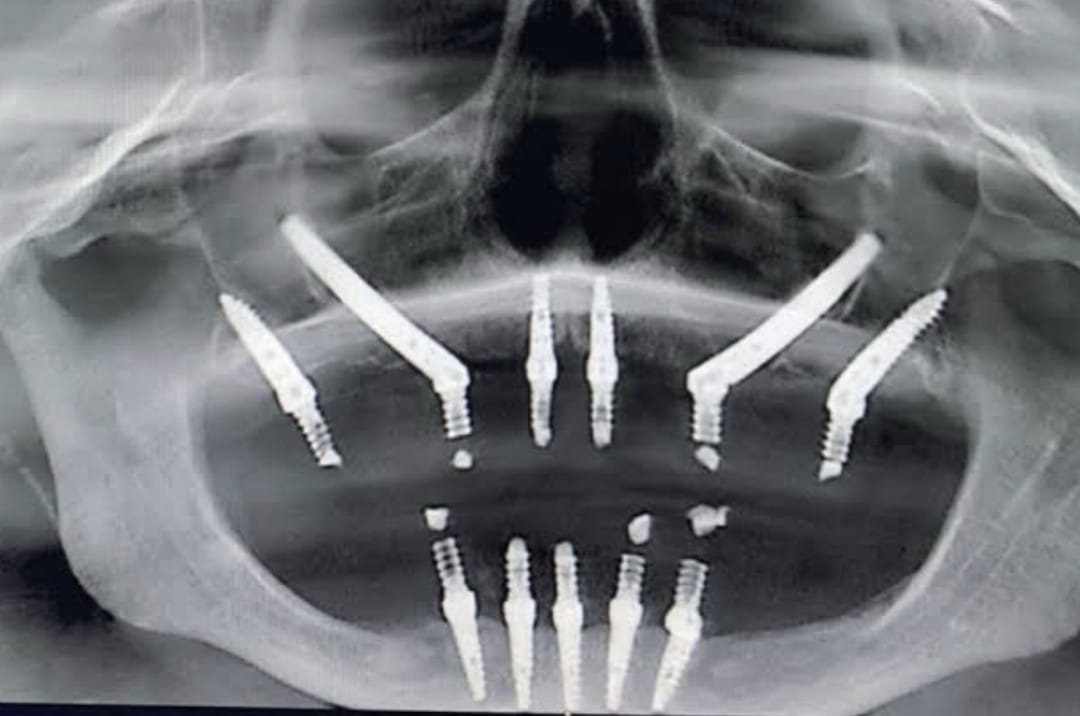

Dental implants are a modern and reliable solution for replacing missing teeth. They are designed to restore both the appearance and function of natural teeth. A dental implant consists of a small titanium post that is surgically placed into the jawbone, where it acts as an artificial root for the missing tooth. This procedure helps provide a stable and long-lasting foundation for the replacement tooth.